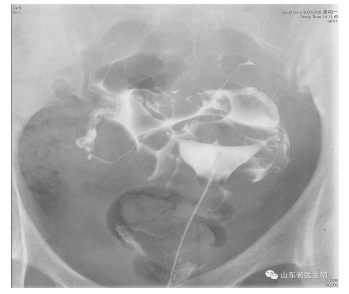

经X线的子宫输卵管造影是通过导管向宫腔及输卵管注入造影剂,利用X线透视及摄片,根据造影剂在输卵管及盆腔内的显影情况来了解输卵管是否通畅、阻塞部位及宫腔形态的一种检查方法。

子宫输卵管造影图